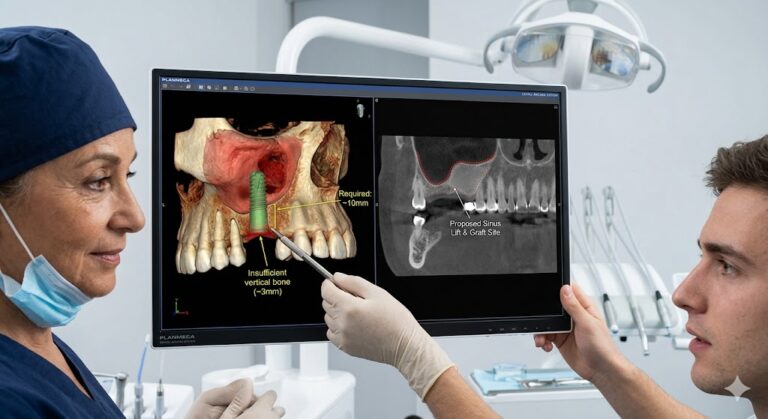

Bone Grafting and Sinus Lifts

Bone grafting procedures present a unique challenge. The surgeon harvests bone particles, often from the patient’s own body or a cadaveric or synthetic source, and packs them into a defect. The sinus lift involves gently elevating the sinus membrane from the floor of the sinus cavity. This membrane tears easily. Coughing or sudden movement can cause catastrophic membrane perforation.

A deep level of sedation helps the patient remain utterly motionless. However, the provider must avoid high levels of nitrous oxide if they have closed off a sinus communication. Pressure changes can distend the sinus. A skilled anesthetic provider balances a motionless patient with the physiological requirements of delicate membrane surgeries. You will likely not be awake for this. The precision demands it.